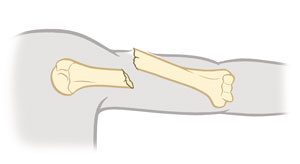

Fractura conminuta

El hueso se ha partido en 3 o más fragmentos.